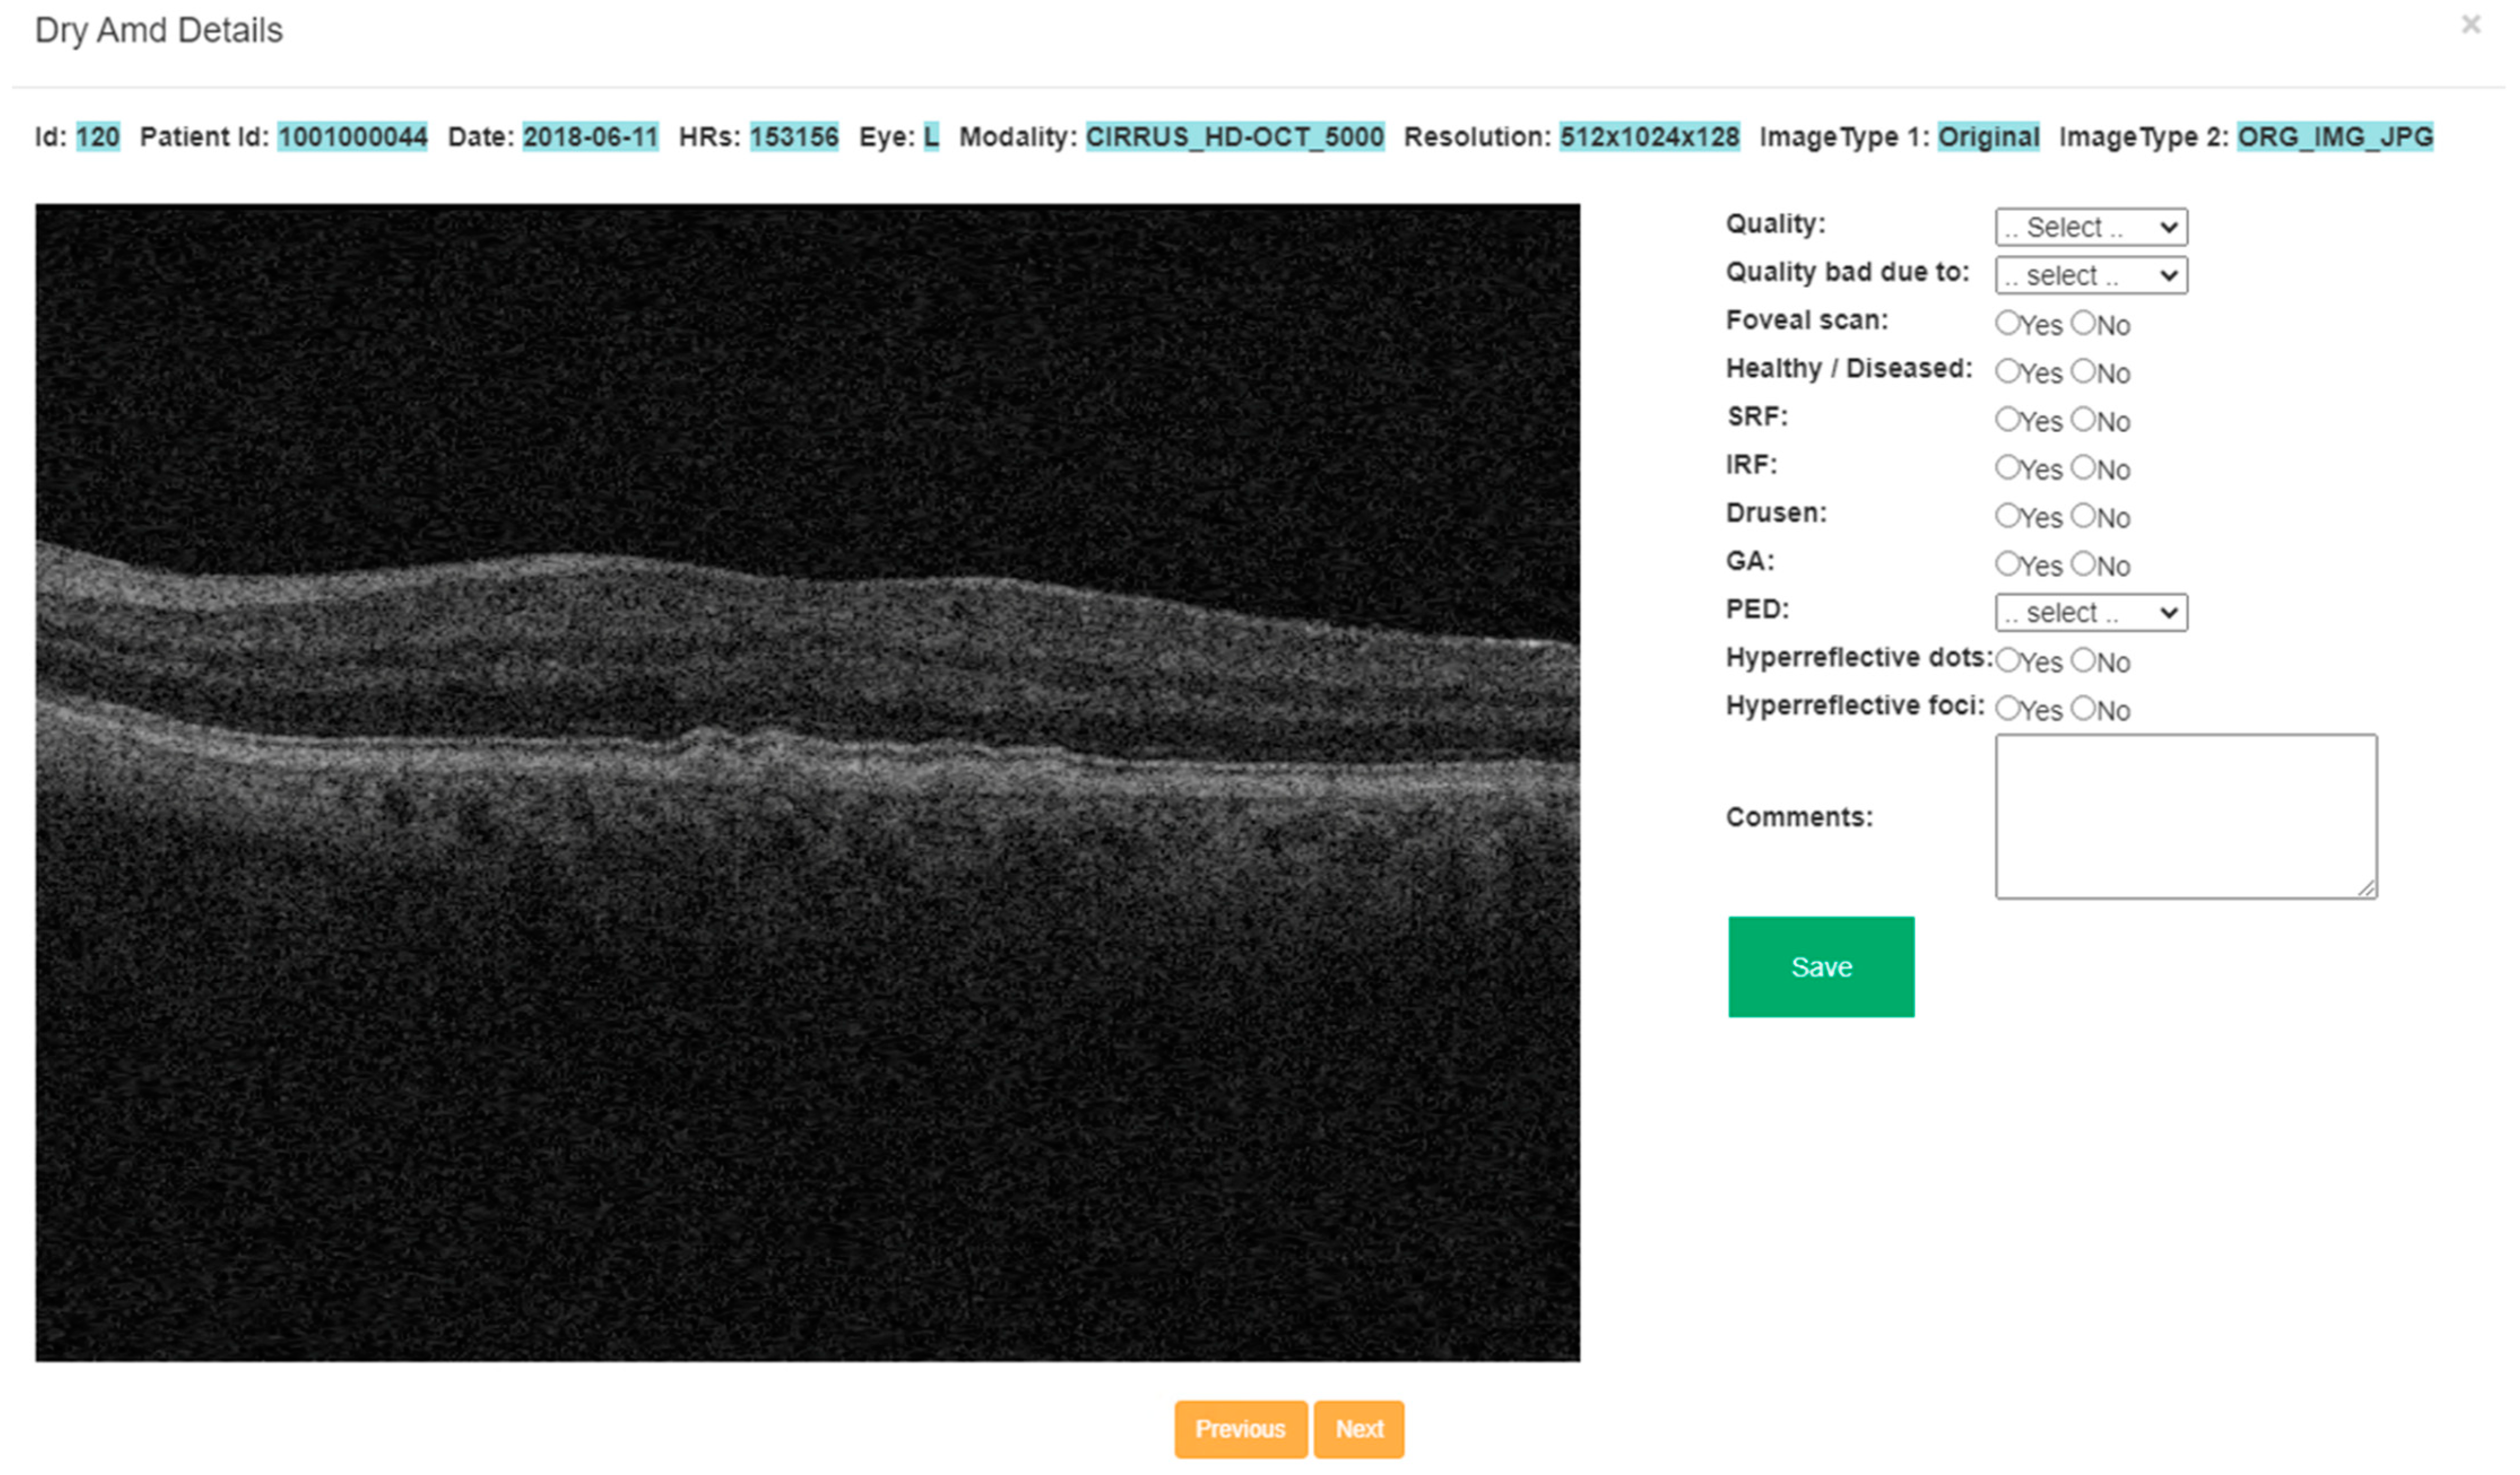

2.3. Annotation Tool